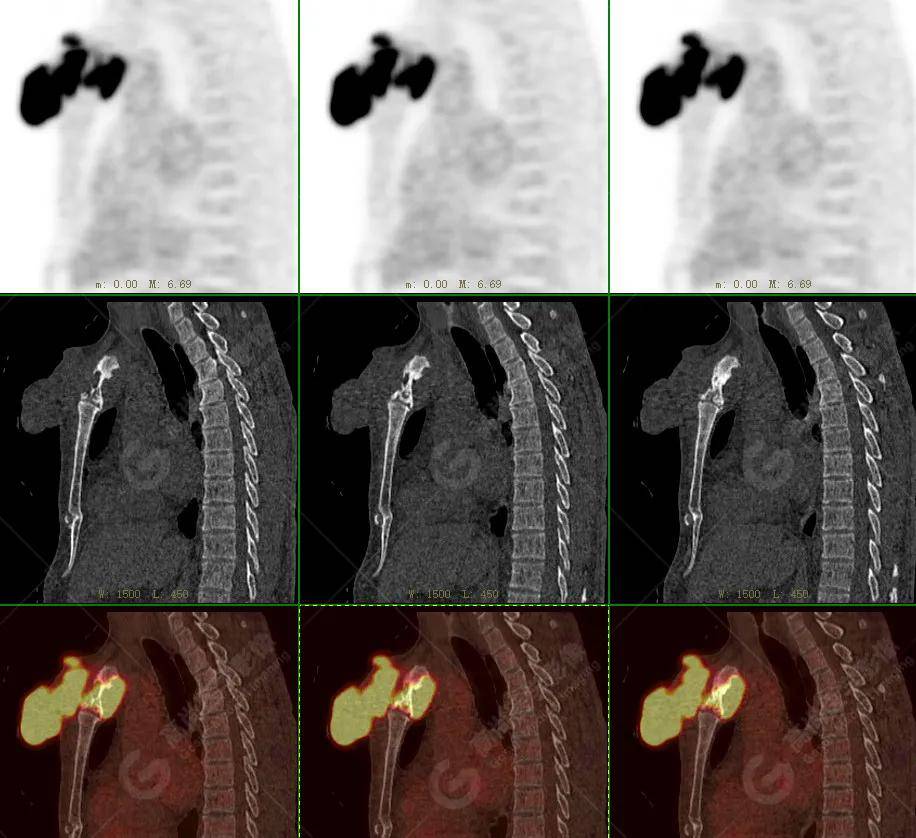

【高尚病例】18f-fdg pet/ct显像应用于骨结核

图片尺寸926x873